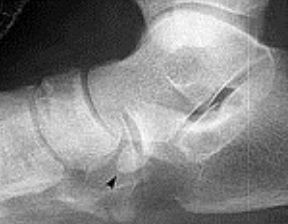

| What is this? | Calcaneonavicular coalition (AKA calcaneonavicular bar or anteater's nose) |